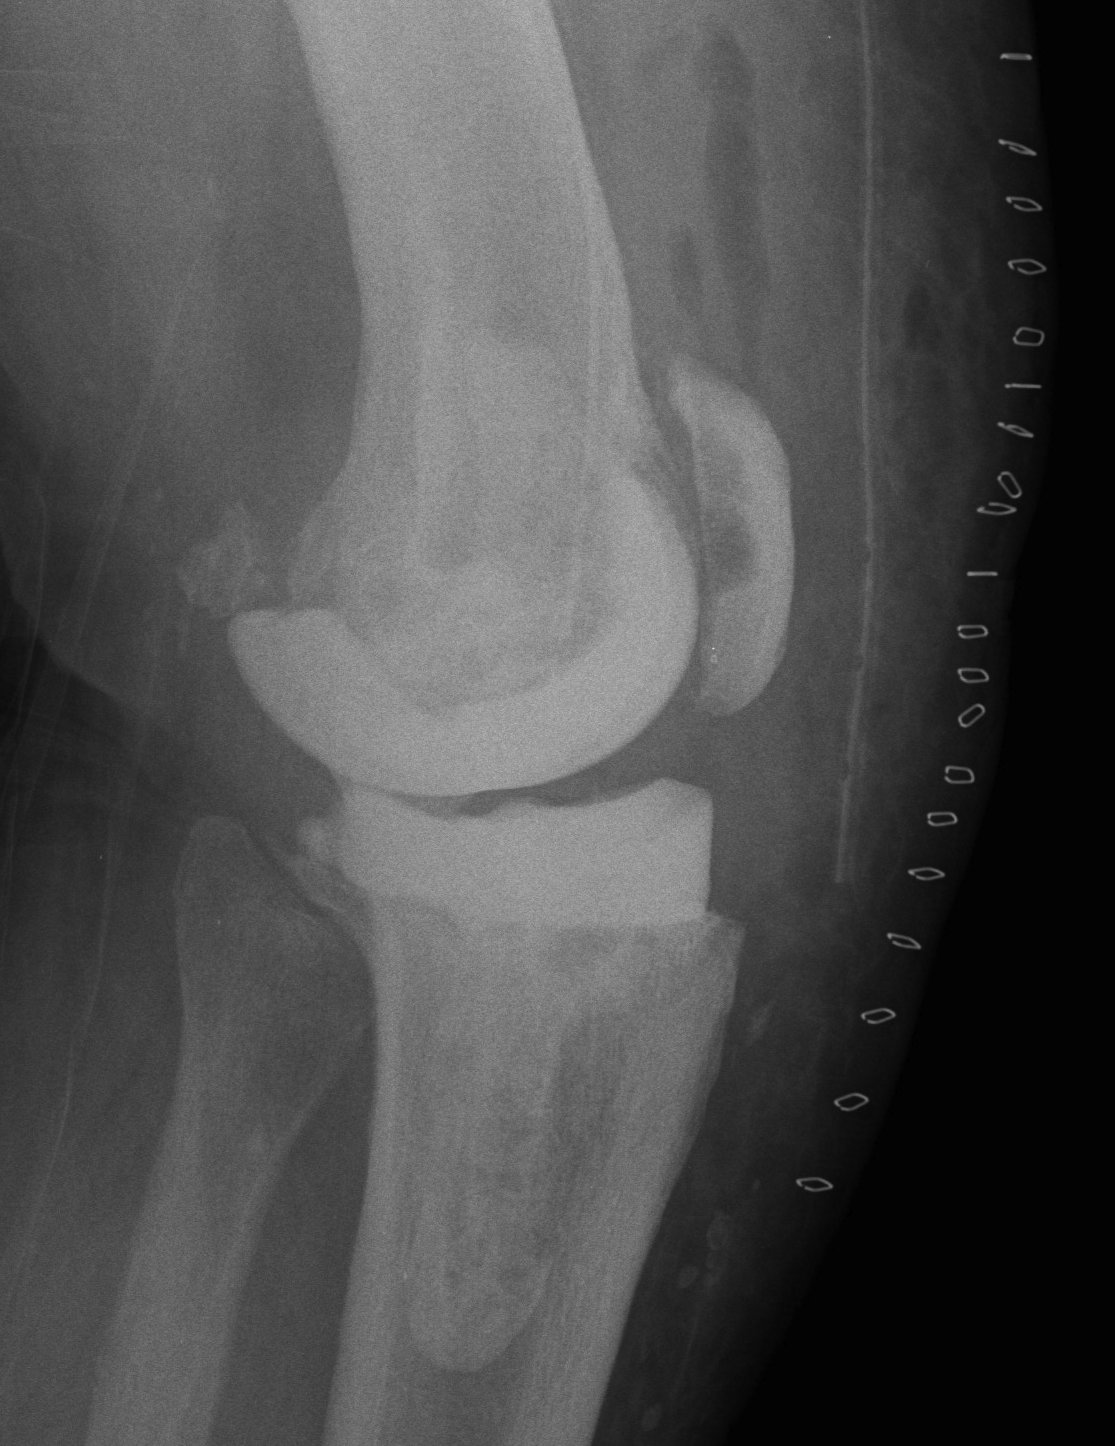

Xray

- progressive early lysis